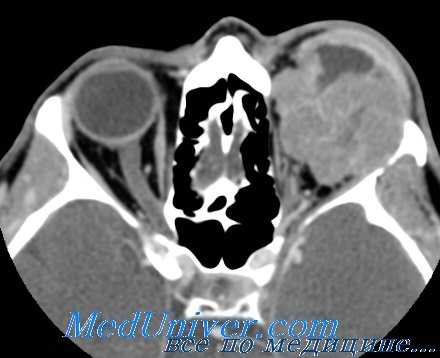

Обследование больных с опухолью глазницы. Крайне полезно провести рентгенографическое и томографическое обследование глазницы, в результате которого можно будет сделать заключение о состоянии глазницы и зрительного канала.

При проведении КТ это заключение может быть детализировано, поскольку будет получена информация о локализации, размере и степени распространения опухоли в пределах (и вне пределов) глазницы. При этом также получают сведения о степени эрозии кости и поражения мягких тканей. Ультразвуковые исследования могут помочь быстро обнаружить опухоль. По возможности следует проводить биопсию, однако она сопряжена с риском диссеминации опухоли, возникновения геморрагии и развития слепоты. При наличии инкапсулированной опухоли ее лучше всего удалить.

Псевдоопухоль глазницы

Обычно при этой патологии развивается болезненная офтальмоплегия, которая часто сопровождается отеком века. При КТ-исследовании в задней части глазницы обнаруживается, как правило, аморфное новообразование, окружающее глазной нерв. Гистологически оно представляет собой полиморфный воспалительный инфильтрат, в котором иногда можно обнаружить монотипичные В-клетки, характерные для низкозлокачественной лимфомы

Гематологическим путем опухоль, в первую очередь, распространяется на легкое или в кость, однако это наблюдается реже, чем при рабдомиосаркомах другой локализации. В 25% случаев регистрируется поражение лимфатических узлов, особенно глубоко расположенных верхних шейных и пред-ушных. Часто отмечается быстрый рост опухоли, приводящий к тяжелому проптозу, хемозу и отеку века. Перед началом лечения необходимо, если возможно, попытаться установить стадию развития опухоли и провести пункцию костного мозга.